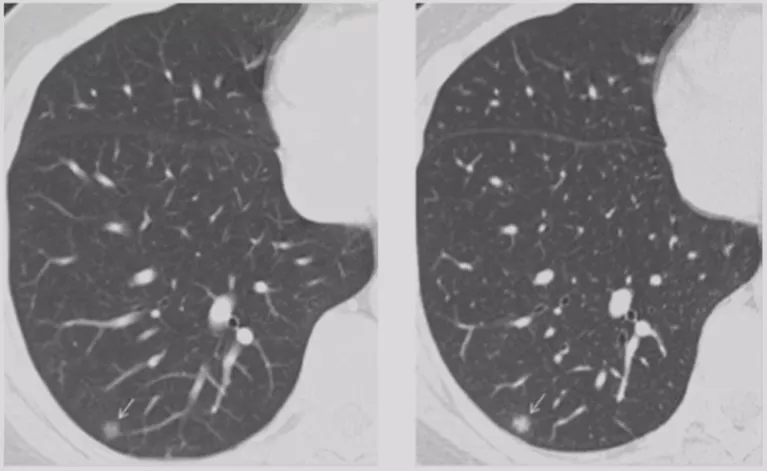

如上图所示,一般来说这么小的病灶我们可能忽略,但这个病人做了手术,不仅是恶性肿瘤,而且是微浸润腺癌。实际上我们在临床上要把这么多结节甄别出来,是十分具有挑战性的。病人一旦患有肺结节,也面临着很多问题,比如焦虑、心理压力等。所以我们既不能过度诊断,但也不能延误诊断。